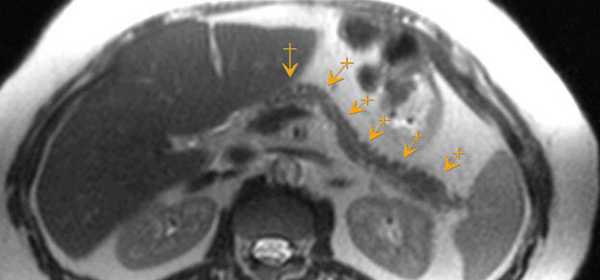

МРТ — магнитно-резонансная томография — применяется реже, чем КТ, так как это более сложное исследование, требующее специального оборудования, которое есть не в каждой клинике. При подозрении на опухоль поджелудочной железы применяют разные модификации МРТ:

- МРТ-холангиопанкреатография позволяет изучить поджелудочную железу и окружающие ткани.

- МРТ-ангиография представляет собой исследование сосудов.

Магнитно-резонансная томография

Вместо компьютерной томографии возможно проведение магнитно-резонансной томографии, но обязательным условием является применение внутривенного контрастирования.